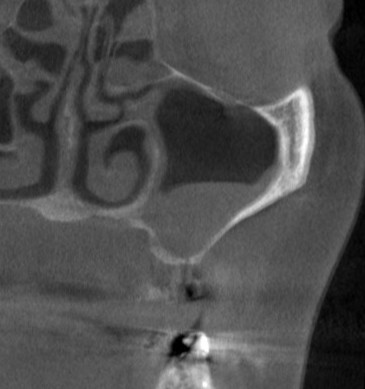

後ろ2本の骨の高さは確保できましたので、インプラント埋入を行ないました。

1本目の部位では、インプラント埋入と同時に、側方に人工骨を補填して骨幅を拡大する造成術を併用して、3本のインプラント埋入が終了しました(下の写真、4段目)。